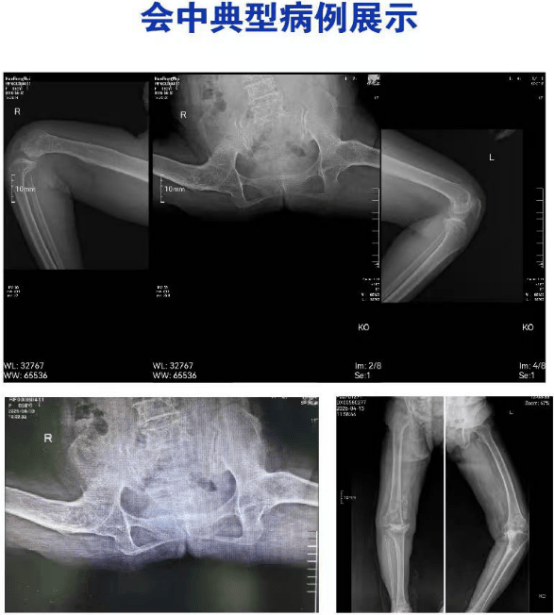

本期讨论会围绕两例极具挑战性的疑难病例展开:“双髋螃蟹腿样畸形融合” 与 “重度内翻伴缺损膝骨关节炎” 。患者病情复杂、关节畸形严重、治疗难度高。

会上,我院关节中心医生首先详细汇报病例资料及初步诊疗思路。随后,来自北医三院骨科关节外科的田华教授专家团队与我院关节中心团队通过线上线下联动,从发病机制、影像学读片、治疗方案、手术入路、假体选择到围术期康复,逐一进行多维度、深层次剖析。